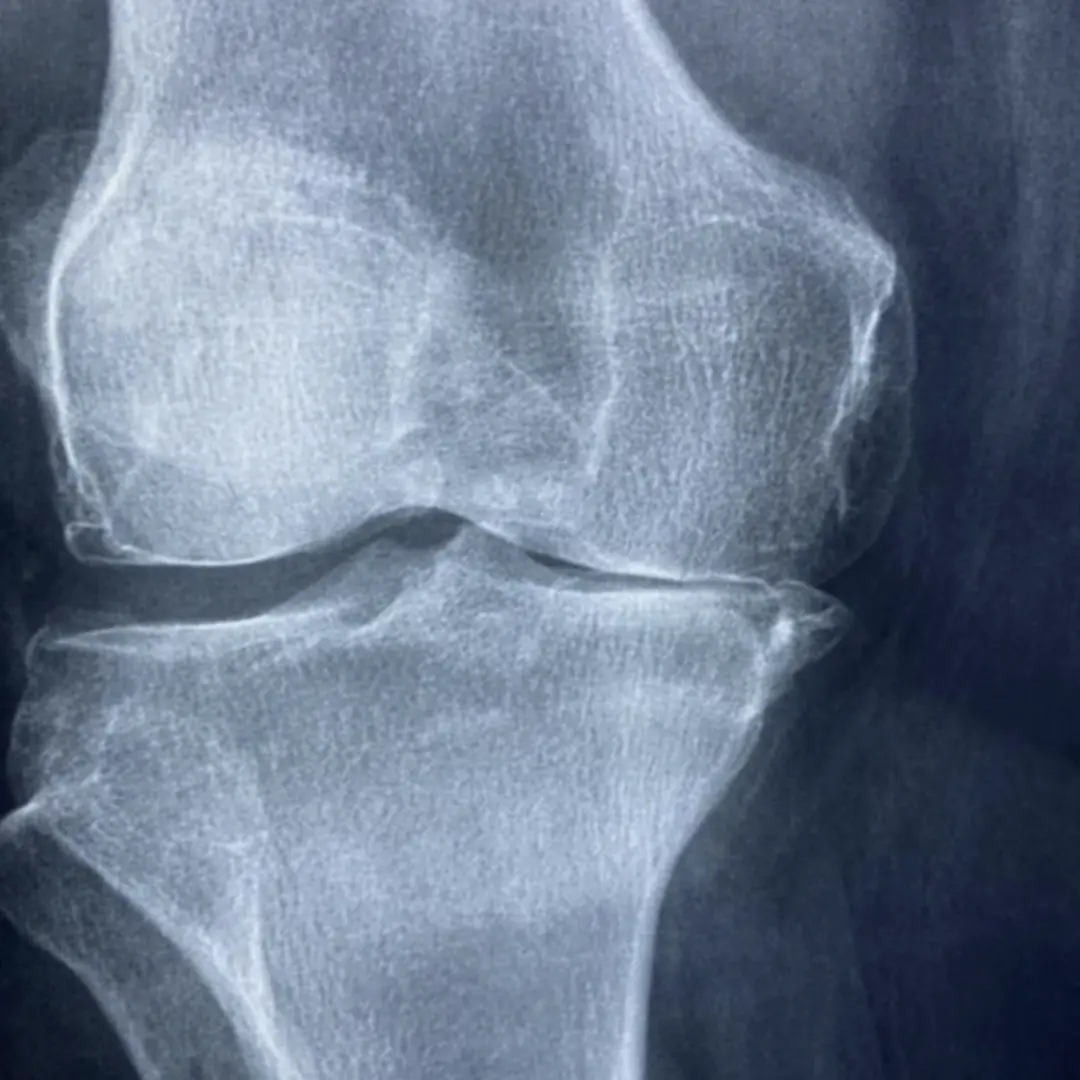

- 관절염 환자: 퇴행성 관절염, 류마티스 관절염 등 관절염으로 고생하는 분들은 항염 효과가 뛰어난 음식을 꾸준히 섭취하여 통증을 완화하고 염증 진행을 늦추는 데 도움을 받을 수 있습니다. 마치 소방수처럼, 염증을 빠르게 진화하고 확산을 막는 역할을 합니다.

- 무릎 부상 경험자: 과거 무릎 부상을 경험했거나 현재 재활 치료 중인 분들은 연골 재생 및 관절 조직 회복에 도움이 되는 음식을 섭취하여 빠른 회복과 재발 방지에 힘써야 합니다. 마치 건축 자재처럼, 손상된 부위를 튼튼하게 재건하는 데 필수적인 영양소를 공급합니다.